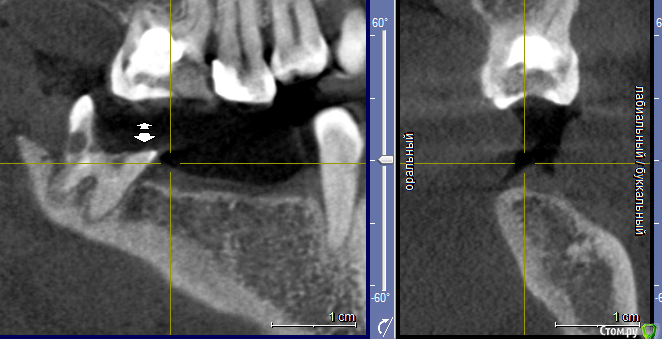

elesilchenko@yandex.ru Опубликовано 18 октября, 2016 Поделиться Опубликовано 18 октября, 2016 Здравствуйте! Подскажите, пожалуйста, возможна ли дентальная имплантация на НЧ без применения костной пластики? И возможно ли спасти зубы с кистами на ВЧ ?Результаты КТ: http://files.mail.ru/1F70A64348084F03ACC722DA9E76BD2B Ссылка на комментарий

elesilchenko@yandex.ru Опубликовано 18 октября, 2016 Автор Поделиться Опубликовано 18 октября, 2016 Добрый вечер! Я в процессе выбора, кто предлагает базальную имплантацию внизу (ВЧ я пока не рассматриваю к имплантации) , кто съемные протезы это на НЧ. По поводу ВЧ тоже разные мнения: 1. Можно полечить, т.к. проблемы с эндодонтией 16 и 12, где небольшой воспалительный процесс.2. 16 удалить, 12 попытаться полечить. Сунус-лифтинга и костной пластики боюсь. Ссылка на комментарий

IvanK Опубликовано 18 октября, 2016 Поделиться Опубликовано 18 октября, 2016 Судя по скудной информации из скриншотов:кости , скорее всего, будет достаточно Вам нужно найти Врача, которому доверяете и довериться) Сходите на пару-тройку очных консультаций Ссылка на комментарий